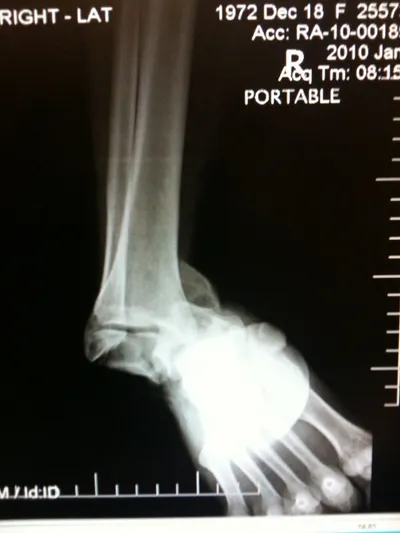

Pictures of a talar neck fracture with displacement of the talar body and subtalar and ankle dislocation prior to surgery